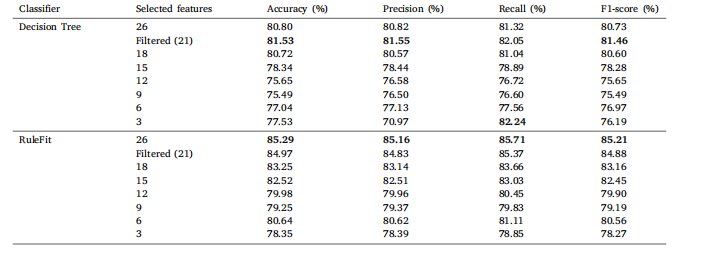

Table 8Classification results of Ultrasound Breast Images for Breast Cancer on a comprehensive set of statistical features with varying feature countsfor DT and RuleFit

表8 基于不同数量统计特征的乳腺癌超声图像分类结果(针对决策树(DT)和RuleFit模型)。